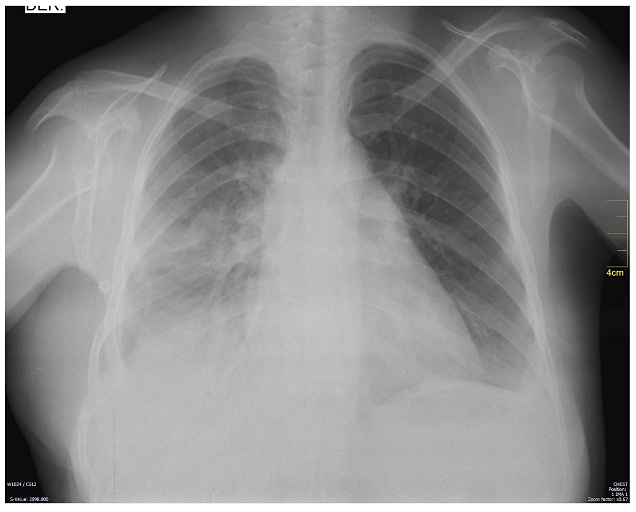

La radiografía de tórax inicial evidenció una opacidad que ocupaba el 70 % del hemitórax derecho, la tac contrastada de tórax evidenció una gran masa sólida de contornos lobulados que comprometía el 70 % del hemitórax derecho de origen extrapulmonar, heterogénea y con densidad de tejidos blandos, que desplazaba el mediastino y comprimía el corazón (figuras 1 y 2). Las dimensiones de la masa eran 16 x 18 x 22cm. Los diagnósticos planteados por el radiólogo fueron teratoma, tumor fibroso pleural o secuestro pulmonar. La histopatología de la muestra, obtenida por biopsia percutánea con aguja cortante de la lesión, reportó un tumor fusocelular de aspecto benigno que pudiera tratarse de un tumor fibroso de la pleura; posteriormente, la inmunohistoquímica confirmó el diagnóstico por inmunoreactividad de las células tumorales para bcl2, cd34, cd99 y stat6 compatible con un tumor fibroso solitario.

En estudios preoperatorios: el ecocardiograma transtorácico reportó una masa extra cardiaca que comprimía la aurícula derecha, fevi 63 %, insuficiencia mitral leve, no trombos intracavitarios. Se consideró candidata para manejo quirúrgico y fue llevada a resección por toracotomía posterolateral derecha extendida asistida por video (cirugía de tórax oncológica), encontrándose un tumor dependiente de la pleura parietal derecha de aproximadamente 30 x 25 x 20cm (figura 3), con adherencias laxas y firmes a pleura parietal, lóbulo inferior del pulmón derecho y hemidiafragma derecho. Vasos de irrigación provenientes de la pleura parietal y del lóbulo inferior derecho del pulmón y escaso líquido serohemático libre en la cavidad. Presento un sangrado intraoperatorio estimado de 1000cc, la cirugía se completo sin otras complicaciones. Fue trasladada a la unidad de cuidados intensivos sin soporte vasopresor y con ventilación mecánica invasiva con parámetros bajos. La evolución clínica y radiológica (Figura 4) fue satisfactoria y su egreso hospitalario se registró al sexto día postoperatorio.

A la fecha, completa 4 meses de seguimiento clínico; sin signos de recidiva local y con una adecuada evolución postoperatoria (figura 4).

Nota: muestra una re-expansión pulmonar derecha y reposicionamiento del mediastino.